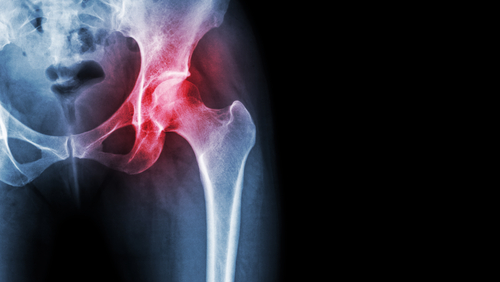

CBD and recovery after hip surgery

Hip problems

Hip replacement surgery is one of the most common surgeries anywhere in the world. In the USA alone, doctors perform more than 450,000 such procedures a year, and in the Czech Republic it is nearly 10,000. However, the waiting time exceeds two years and hospitals are full long in advance, which is a problem for elderly patients or those whose health condition requires acute intervention. The average age of patients is around sixty-five years, but in recent years much younger people have been appearing in the operating theatre, so it is not uncommon for people twenty years younger to undergo the operation.

That hip replacement is so common is not surprising. It is a highly stressed joint that connects the lower limbs to the trunk and is under pressure when walking and sitting. While the muscle tissue and cartilage protect the joint and prevent it from wearing out quickly, the hip becomes more vulnerable as we age.